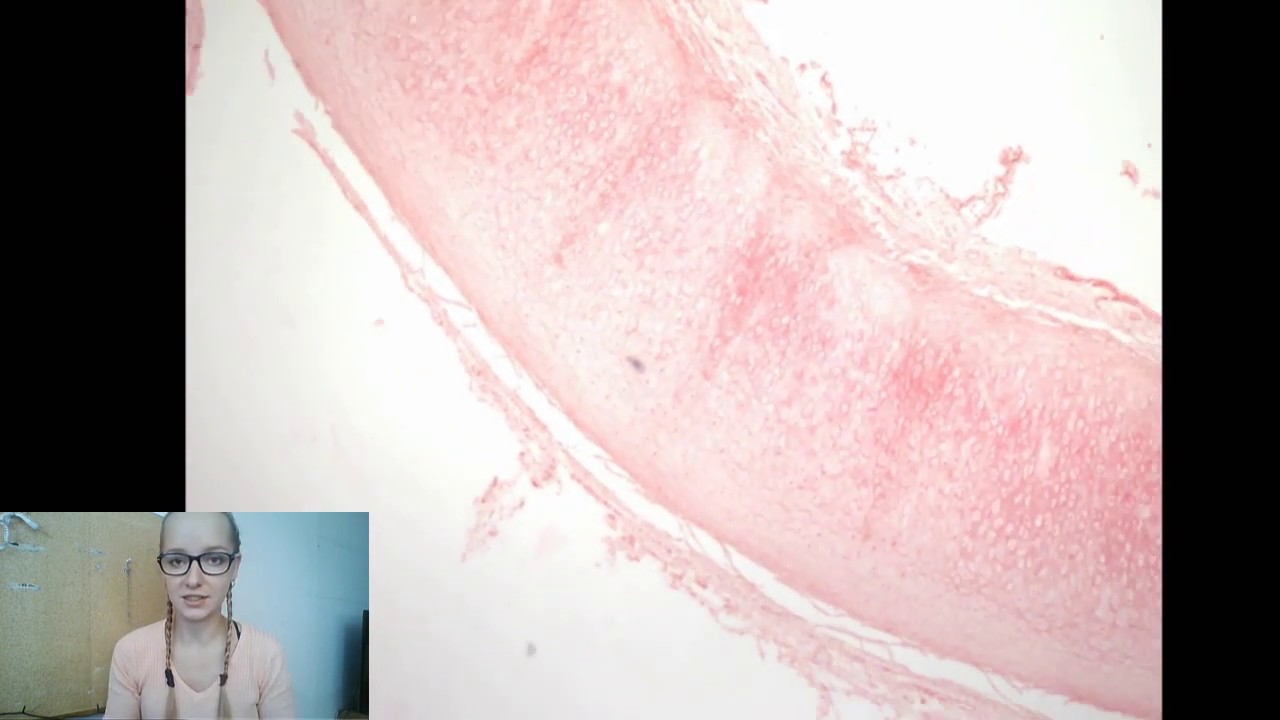

Popis histologického preparátu žlučníku. Stěna žlučníku je členěna na sliznici, svalovinu a adventitii/serosu. Sliznice vytváří řasy a obsahuje krypty (Rokitanskeho-Aschoffovy sinusy). Povrch sliznice je kryt jednovrstevným cylindrickým epitel s mikroklky, který slouží k zahušťování žluči. Výživu epitelu zajišťuje lamina propria (řídké kolagenní vazivo). Pod ní je uložena vrstva hladké svaloviny. Poslední vrstvou je kolagenní vazivo - adventitia nebo serosa. V tomto případě je to serosa (vazivo je ohraničené mezotelem). Barveno: modifikovaný zelený trichrom Autor: Mgr. Tereza Blassová, Ph.D. Pořízení skenu preparátu: Mgr. Yaroslav Kolinko, Ph.D.